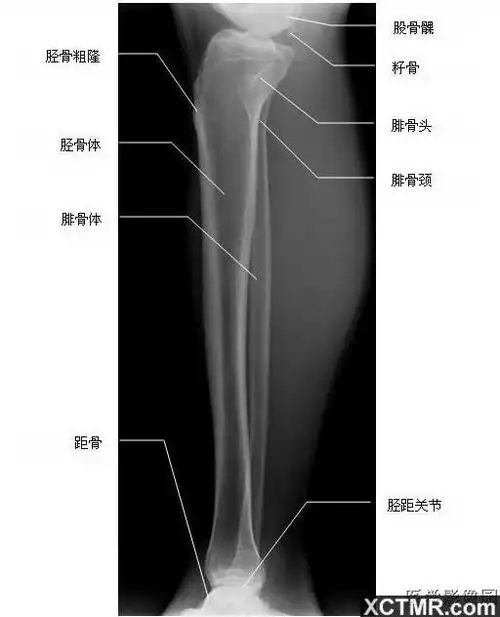

胫腓骨正位x线

【工作必备】x线解剖图谱 系统解剖(骨骼篇),非常全面,强烈建议收藏

胫腓骨侧位-x线-解剖图片